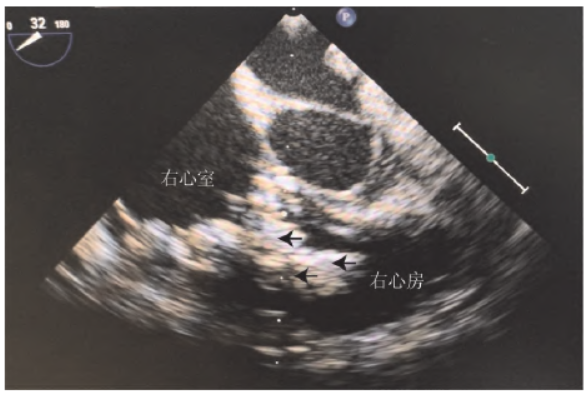

术前3 周患儿出现胸痛症状,血管超声检查发现右侧颈内静脉与锁骨下静脉交汇处的管壁周围有沉积物、腋静脉内实质占位,CT 发现双侧下肺动脉分支有多发栓塞,遂开始抗凝治疗。术前1 周心脏超声检查发现三尖瓣附着物变大、三尖瓣返流增加、心脏增大、心包积液(图1),术前1 d 患儿出现心率加快、少尿、呼吸困难等表现,考虑到内科治疗效果欠佳与持续等待存在的风险,决定行外科手术治疗。

图1 术前超声心动图检查